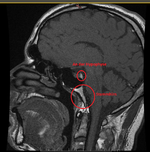

Weil ich Angst habe das mein Hirn von Schwermetalle geschädigt ist, und die Radiologie es nicht sieht ( weil die Microweiße Punkte im Hirn keiner Bedeutung zuweisen, diese sich aber über kurz oder Lang vergrößern können) habe ich die CD's der beiden MRT's aus den letzten beiden Jahren angefordert und möchte mittels Daunderers Bildmaterial mein Hirn mal vergleichen. Vielleicht erkenne ich ja Auffälligkeiten.

Um ein Microadenom auszuschließen erfolgt MRT 3 in den nächsten 4-8 Wochen. Dabei begleitet mich ein Neurologe der mir dann hoffentlich auch mal Diazepam verschreibt. Ich möchte das Zeug unbedingt testen und in wirklich schwierigen Zeiten so wie gestern und heute einfach mal 2 Tage nehmen um ne Pause von meinen Rückenproblemen zu haben. Plan sind 2-4 Einnahmezyklen pro Monat jeweils über 2 Tage um keine Abhängigkeit zu riskieren. Die Nebenwirkungen sind deutlich milder als bei Ortoton.